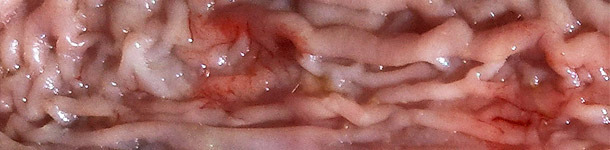

Respostas sobre pleuropneumonia por App (2/2): diagnóstico, monitorização e erradicação

Neste segundo artigo Antonio Vela, Francisco José Pallarés e David Espigares respondem a perguntas sobre diagnóstico, monitorização e erradicação da pleuropneumonia causada por Actinobacillus pleuropneumoniae (App).